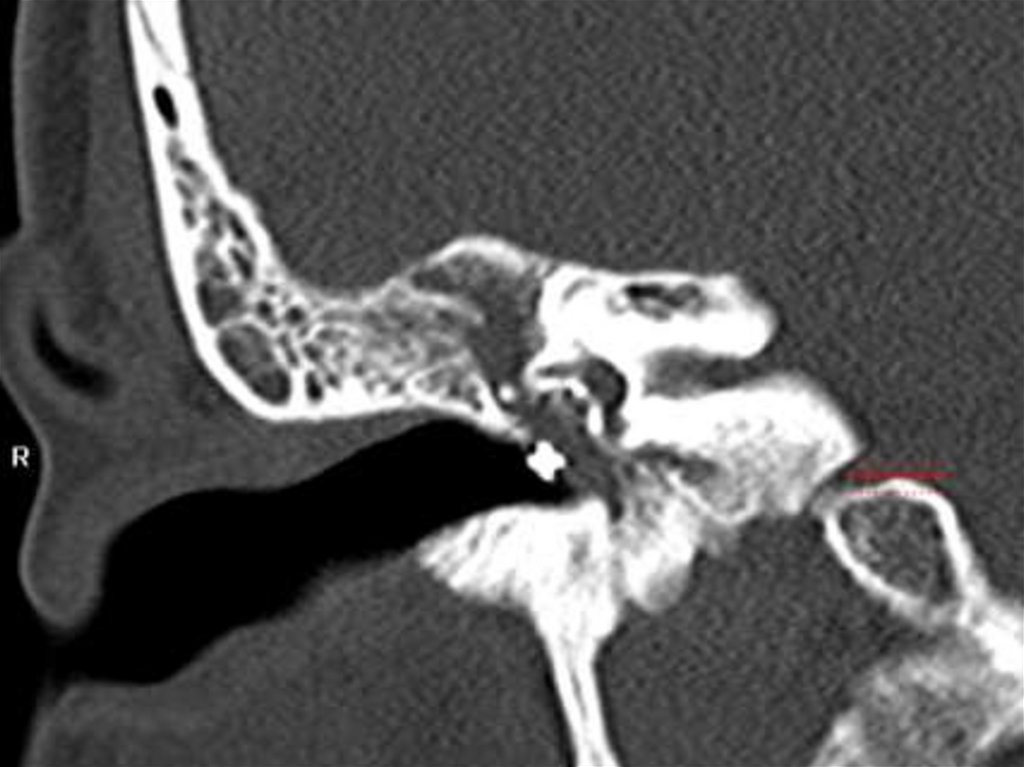

152. Стеноз наружного слухового прохода

Пороки развития

Стеноз наружного слухового

прохода

153. Стеноз НСП